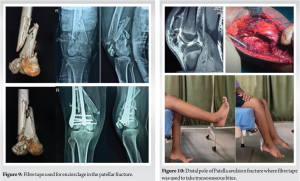

The patella serves as a pivotal component in the biomechanical function of the knee extensor apparatus [1]. Fractures of the patella have the potential to disrupt this mechanism, particularly when combined with incongruent posterior articular surfaces, leading to persistent issues like discomfort arising from femoropatellar arthritis [2,3]. Patellar fractures commonly stem from two primary mechanisms: Direct impact on the anterior knee or indirect injury resulting from eccentric contraction of the quadriceps muscle [4]. Surgical intervention becomes necessary in about one-third of patients affected by these fractures. Tension band wiring using stainless-steel wires has long been considered the gold standard for surgically managing displaced patellar fractures (Fig. 1 and 2) This technique effectively converts tension from muscle pull into compression at the fracture’s articular side, promoting improved fracture union by providing absolute stability through interfragmentary compression in bending fractures. However, its widespread use has been subject to debate due to the high incidence of resurgery rates attributed to issues such as implant impingement, skin infection, and wire breakage [5,6] (Fig. 3 and 4). Also for multifragmented stellate fracture, where encircle is required, SS wires require multiple passes through retinaculum with 4-mm-thick wire passer which is more traumatic. An alternative to traditional metal wire for patellar fracture fixation is non-absorbable suture, such as fiber tape (Fig. 5), which has been shown to yield similar outcomes with a reduced complication rate and comparable strength in biomechanical studies. Multiple passes in encirclage method for comminuted fractures with fiber tape is less traumatic with 2-mm needle. Research conducted by Arthrex found that fibreTape exhibited significant strength at 3 mm elongation and shows good loop integrity [7].

In comminuted fractures where encirclage is preferred, the fiber tape is initially threaded beneath the patellar tendon before being wrapped circumferentially around the patella bone. Utilizing a tensioner, the fiber tape is then tensioned to a force of 70–90 pound force (Fig. 6). Subsequently, the reduction is assessed intraoperatively, knots are securely buried under the retinaculum, and excess is trimmed after checking the stability of the reduction by performing flexion and extension movements of the knee (Fig. 7).

Following the surgical procedure, the knee is secured in a long knee brace for 4 weeks, with suture removal scheduled at 14 days. Partial weight bearing with assistance is permitted after 2 weeks. Subsequent check-ups occur at 3-week and 6-week post-surgery. At 4 weeks, range of motion exercises is commenced with a focus on restoring active knee flexion. Rehabilitation progresses with active flexion movements at 5 weeks, culminating in the conclusion of care at 12-week post-surgery (Fig. 8-10).

Operative intervention is necessary for every unstable patellar fracture. Tension band wiring, aligning with AO principles, stands as the most widely accepted technique for treating displaced patellar fractures. However, various other methods combining fixation techniques such as K-wires, screws, and cerclage wiring have been documented. Internal fixation is crucial for maintaining fracture reduction until complete healing is achieved, while conventional stainless-steel wires can offer stability, their use often leads to symptomatic hardware and other complications [8]. Consequently, alternative materials with superior tensile strength, as demonstrated in biomechanical studies, have been investigated. Fiber tape, a braided tape shaped polyblend suture, exhibits a tensile strength exceeding 540N, surpassing the 494 N strength of 18 gauge steel wires. Furthermore, testing with cadaveric tendons revealed a pull through force of approximately 189 N for fiber tape, Notably displacement of hardware with stainless-steel wires, resulting in hardware prominence [9,10]. Utilizing fiber tape eliminates the need for implant removal due to skin impingement, addressing a common issue associated with metallic wires. Furthermore, fiber tape exhibits resilience without fatigue, lesser tissue damage, minimizing the risk of implant failure often observed with metal wire breakage and if encirclage is the treatment of choice then it is MRI compatible also [10,11]. Moreover, unlike fixation with metallic wires, fiber tape can be employed not only for simple or comminuted patellar fractures but also as an effective fixation method for distal pole avulsion fractures (Fig. 10-12). However, it is worth noting that the tightness of the fixation knot is surgeon dependent, posing a potential drawback. This issue can be addressed by implementing multiple sequential tightening of 3–4 reverse half hitches on alternating post knots to ensure optimal fixation [12,13]. In our study, we observed a notable decrease in the number of patients requiring re operation, resulting in reduced strain on resources and financial benefits for the patients.